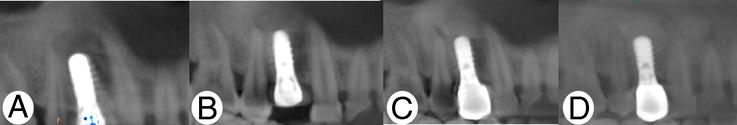

The patient, a female, 49 years old, right upper posterior tooth missing for 1 year, through the maxillofacial surgery consultation, according to the imaging data, the maxillary fibroskeletal lesions were considered. The tumor was removed, bone regeneration was guided, and microimplants were implanted at the same time. Cone Beam Computed Tomography was performed at 3, 9, and 20 months postoperatively, and according to clinical evaluation, the patient did not show any signs of recurrence. At the same time, a literature search was conducted to summarize the data on simultaneous implantation therapy for fibroskeletal lesions of the jaw.

患者为49岁女性,右上后牙缺失1年,经颌面外科会诊,根据影像学资料,考虑为上颌骨纤维-骨性病变。切除肿瘤,引导骨再生,并同期植入微型种植体。术后3个月、9个月和20个月进行锥形束计算机断层扫描,根据临床评估,患者未出现任何复发迹象。同时进行文献检索,总结颌骨纤维-骨性病变同期种植治疗的数据。